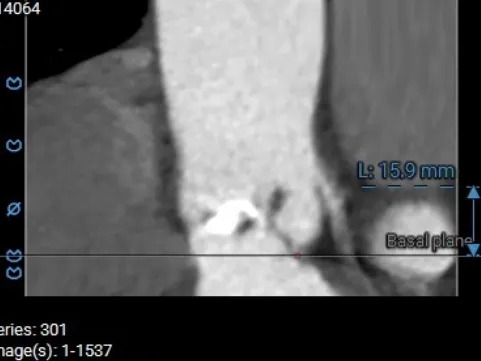

术前CT测量

主动脉根部测量

Annulus 21.3mm

LVOT 26.4mm

钙化积分 399

SOV

31.7*34.7*33.8mm

STJ 31.6mm

AAO 37.4mm

多平面结构测量

瓣下2mm

22.2mm

瓣上2mm

21.8mm

瓣上4mm

23.4mm

瓣上6mm

23.1mm

瓣上8mm

23mm

瓣上10mm

25.7mm

冠脉风险评估

LCA Height

RCA Height

冠脉开口高度可,结合瓦氏窦大小,预估冠脉风险相对较低。